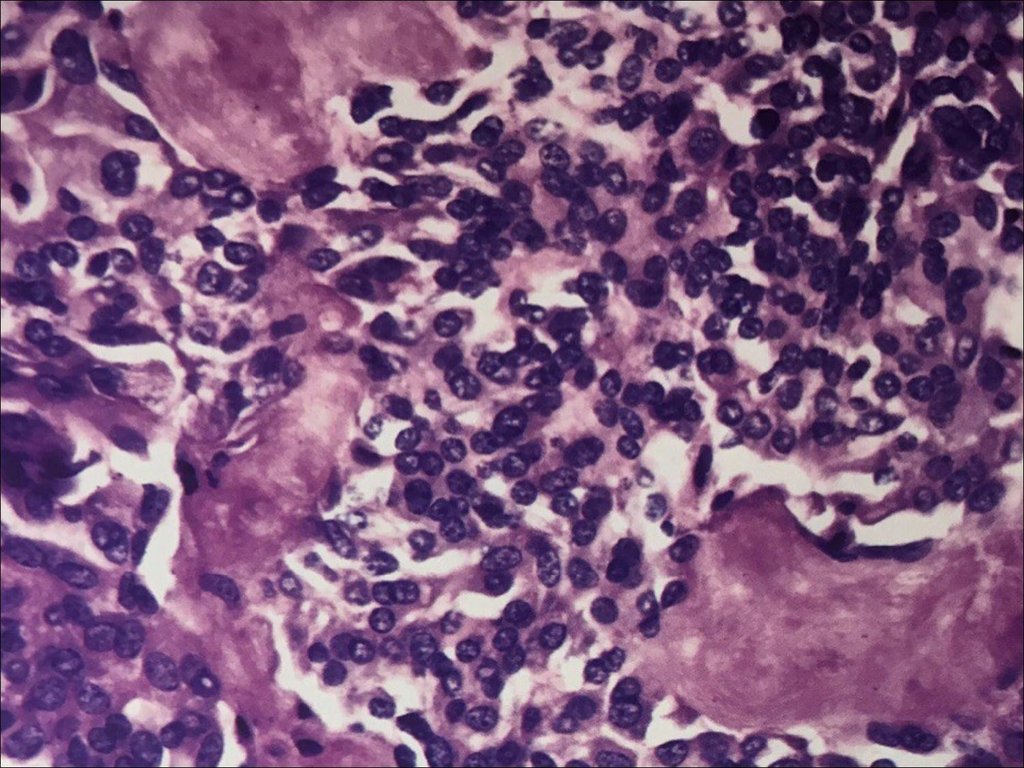

Фотографии опухоли медуллярной аденокарциномы